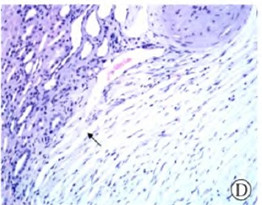

平滑肌肿瘤并不少见,多发生于子宫、胃肠道、脉管等平滑肌丰富的脏器,但原发于肾脏的十分罕见。据尸检结果研究发现平滑肌瘤的发病率是4%~5.5%,其中2/3为女性。白种人的发病率比其他种族的人高。临床上肾脏平滑肌瘤常分为两大类:①大多数是尸检中发现的,或行直径小于2cm的多发的肾皮质肿瘤手术时偶然发现的;②少数是肿瘤大到影像学检查可以发现,或肿瘤大至产生肾区疼痛、叩痛,有肉眼血尿等临床症状时发现。据推测肾脏平滑肌肿瘤最常起源于肾包膜,其次是肾盂,起源于肾脏血管的平滑肌瘤最为罕见。回顾肾脏的组织学特征:肾皮质浅层内呈放射状排列的动、静脉,小动、静脉以及肾小球的人球小动脉和出球小动脉内均含有平滑肌成分。平滑肌细胞也见于肾盂、肾盏及肾脏包膜内层。这为肾脏平滑肌瘤的发生提供了组织学基础。本例肾脏平滑肌瘤位于肾皮质内,其肿瘤细胞成分与肾皮质内的小静脉血管壁的平滑肌细胞之间存在逐步移行过渡融合的区域(图2D箭头所示),故推测本例。肾脏平滑肌瘤是来源于肾脏小静脉血管壁的平滑肌细胞。本例是迄今为止文献报道的第3例起源于肾脏静脉血管壁的良性肾脏平滑肌肿瘤。Yanaihara H等对肾脏平滑肌瘤的患者进行了DNA流式细胞学分析发现其为二倍体分型。比较基因组杂交显示该肿瘤患者存在染色体4、6、12及14的缺失。平滑肌瘤影像学检查多表现为软组织密度实性肿瘤,中等密度,病变与周围组织界限清楚,没有肾外浸润或转移表现,多数位于肾包膜、肾包膜下或肾盂。

图2D 小静脉血管壁与肿瘤之间存在过渡移行区域,如箭头所示(HE×lOO)。